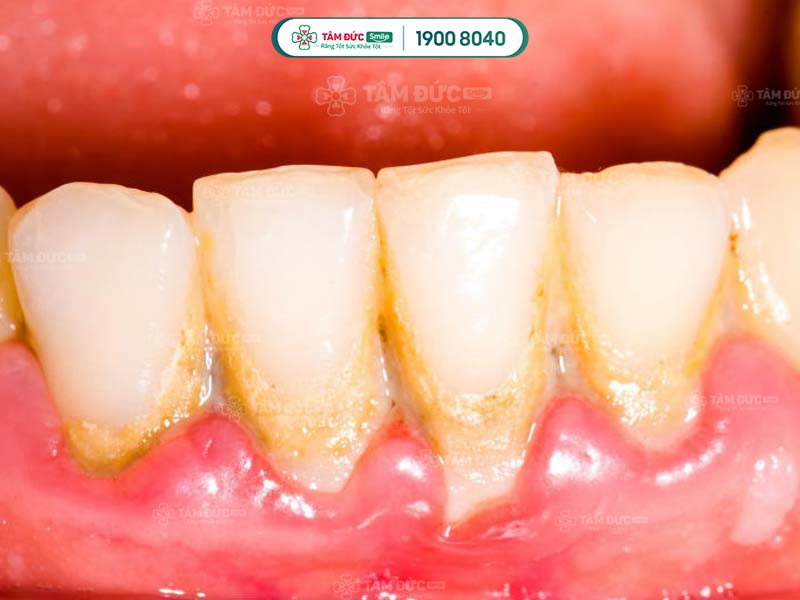

- Phát hiện có nhiều cao răng và mảng bám ở thân răng hoặc dưới nướu.

Cao răng không phải là nguyên nhân trực tiếp gây ra các bệnh lý về răng miệng, nhưng lại là nơi trú ngụ của nhiều loại hại khuẩn. Vì vậy, cao răng tạo điều kiện để vi khuẩn gây bệnh.

Cao răng tích tụ lâu ngày sẽ gây ra các bệnh lý như: Sâu răng, viêm nướu, tụt nướu, mòn men răng, viêm nha chu,... Do đó, cạo cao răng thường xuyên giúp Quý khách ngăn chặn vi khuẩn phát triển, giảm nguy cơ mắc phải các bệnh lý răng miệng.

Cao răng có màu sẫm, tích tụ trên thân răng làm ảnh hưởng đến thẩm mỹ nụ cười. Cạo cao răng giúp Quý khách loại bỏ các mảng bám tối màu, trả lại hàm răng trắng sáng và đẹp mắt hơn.